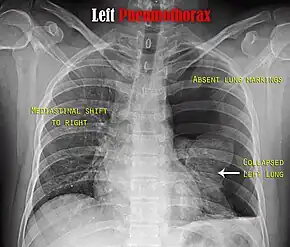

Chest X-ray

A plain chest radiograph, ideally with the X-ray beams being projected from the back (posteroanterior, or "PA"), and during maximal inspiration (holding one's breath), is the most appropriate first investigation.[25] It is not believed that routinely taking images during expiration would confer any benefit.[26] Still, they may be useful in the detection of a pneumothorax when clinical suspicion is high but yet an inspiratory radiograph appears normal.[27] Also, if the PA X-ray does not show a pneumothorax but there is a strong suspicion of one, lateral X-rays (with beams projecting from the side) may be performed, but this is not routine practice.[14][18]

It is not unusual for the mediastinum (the structure between the lungs that contains the heart, great blood vessels and large airways) to be shifted away from the affected lung due to the pressure differences. This is not equivalent to a tension pneumothorax, which is determined mainly by the constellation of symptoms, hypoxia, and shock.[13]

The size of the pneumothorax (i.e. the volume of air in the pleural space) can be determined with reasonable accuracy by measuring the distance between the chest wall and the lung. This is relevant to treatment, as smaller pneumothoraces may be managed differently. An air rim of 2 cm means that the pneumothorax occupies about 50% of the hemithorax.[14] British professional guidelines have traditionally stated that the measurement should be performed at the level of the hilum (where blood vessels and airways enter the lung) with 2 cm as the cutoff,[14] while American guidelines state that the measurement should be done at the apex (top) of the lung with 3 cm differentiating between a "small" and a "large" pneumothorax.[28] The latter method may overestimate the size of a pneumothorax if it is located mainly at the apex, which is a common occurrence.[14] The various methods correlate poorly, but are the best easily available ways of estimating pneumothorax size.[14][18] CT scanning (see below) can provide a more accurate determination of the size of the pneumothorax, but its routine use in this setting is not recommended.[28]

Not all pneumothoraces are uniform; some only form a pocket of air in a particular place in the chest.[14] Small amounts of fluid may be noted on the chest X-ray (hydropneumothorax); this may be blood (hemopneumothorax).[13] In some cases, the only significant abnormality may be the "deep sulcus sign", in which the normally small space between the chest wall and the diaphragm appears enlarged due to the abnormal presence of fluid.[15]